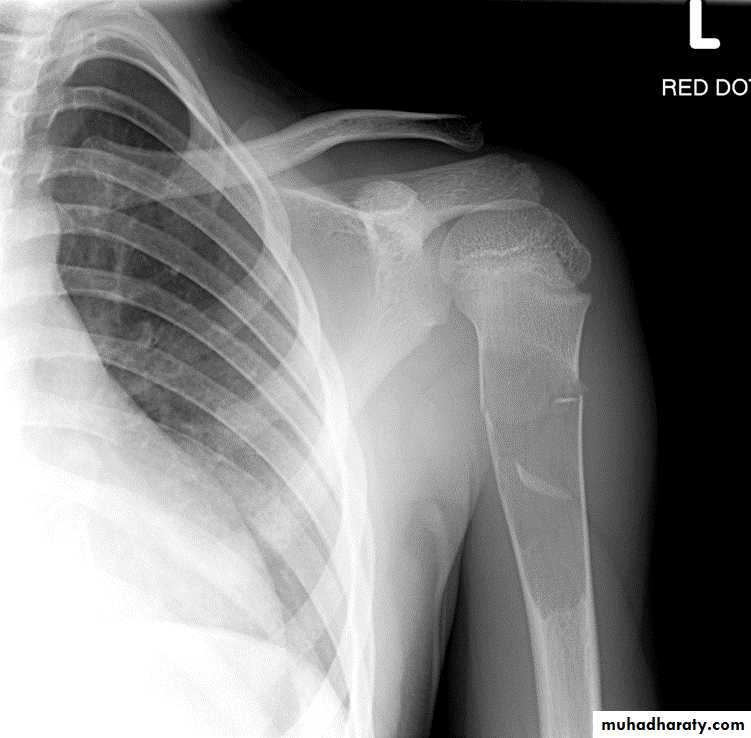

Mushroom Deformity of the femoral neck in perthes disease

being flattened femoral head with a contiguous broad neck, accompanied by awidened articular space .Fallen fragment sign

*Legg-Calve-Perthes disease osteochodrosis of the femur head

*Mushroom deformity of femoral Neck (perthes diseade )